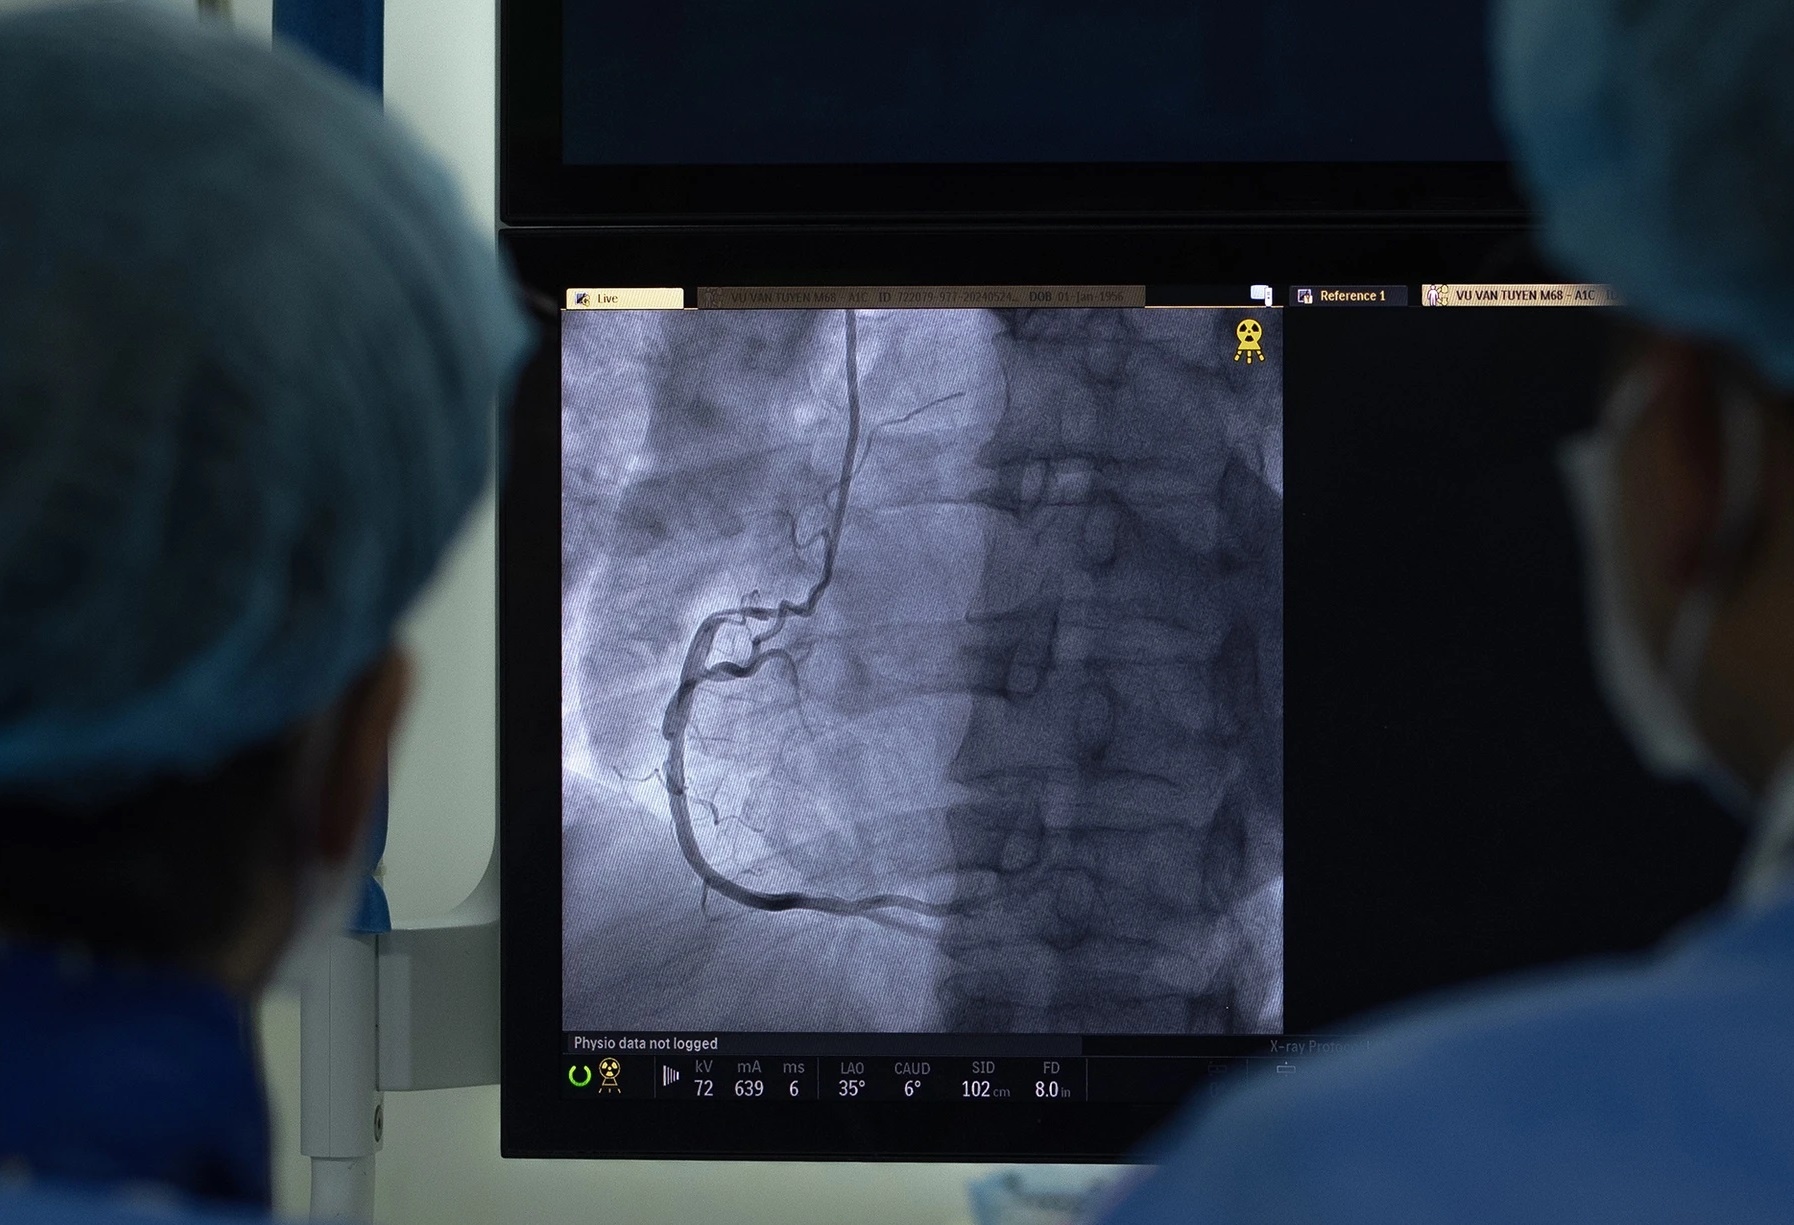

Một ca can thiệp mạch vành cấp cứu cho bệnh nhân nhồi máu cơ tim được thực hiện tại Viện Tim mạch, Bệnh viện Trung ương Quân đội 108. Ảnh: Việt Linh.

Tại bệnh viện, điện tâm đồ và xét nghiệm men tim cho thấy dấu hiệu rõ ràng của nhồi máu cơ tim cấp. Kết quả chụp mạch xác định bệnh nhân bị tắc một nhánh động mạch vành trái - mạch máu quan trọng nuôi dưỡng phần lớn cơ tim trái.

Ê-kíp can thiệp lập tức đặt stent tái thông mạch vành khẩn cấp, giúp khôi phục dòng máu và cứu sống bệnh nhân.

"Đây là minh chứng rõ ràng cho vai trò của 'thời gian vàng' trong cấp cứu nhồi máu cơ tim. Bệnh nhân được can thiệp sớm, cơ hội sống càng cao", bác sĩ Mạnh cho hay.